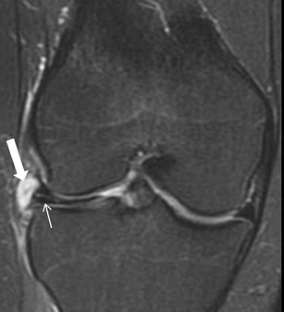

Fig. 4